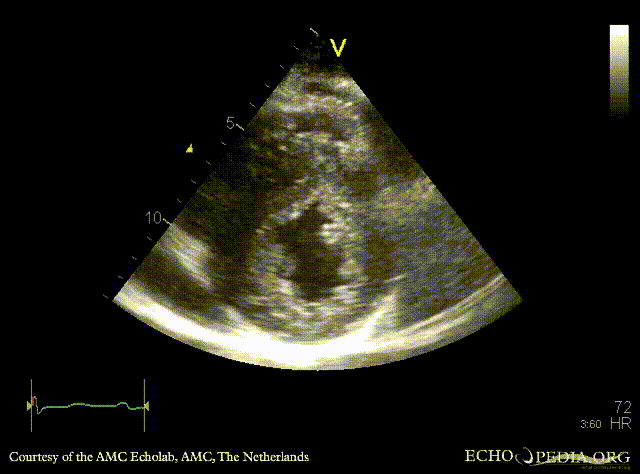

PLAX: severe concentric hypertrophy of left ventricle, SAM of AMVL PLAX zoom: SAM of AMVL